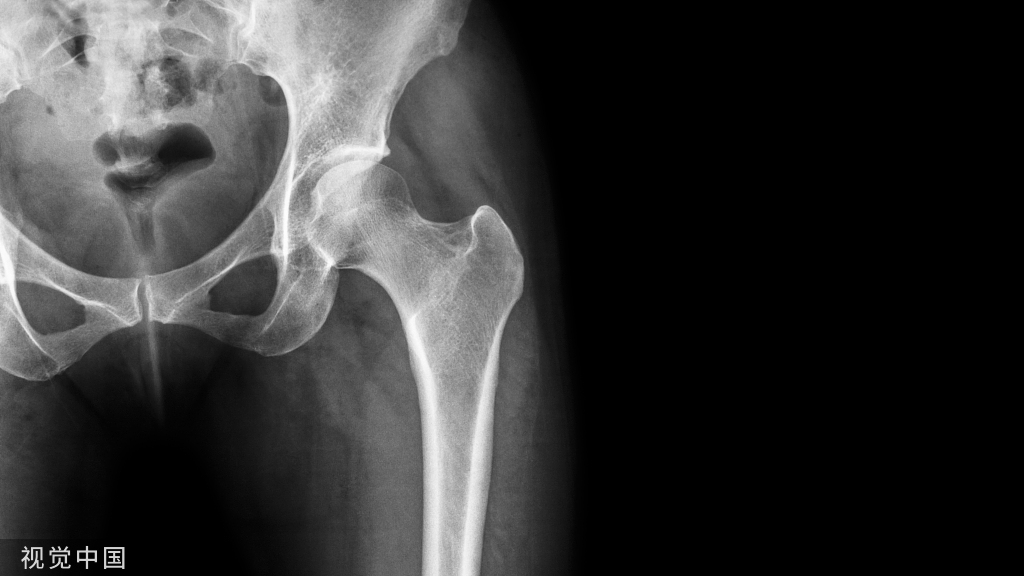

OA是世界范围内患病人数最多的关节疾病,全球总患病人数超过2.4亿,其中我国患病人数超1亿。由于发病机制未明,OA至今缺乏有效的改善病情药物(DMOADs)。

另外团队近期在Osteoarthritis & Cartilage发表的“Evaluating the impact of metformin targets on the risk of osteoarthritis: a mendelian randomization study” 孟德尔随机研究发现,二甲双胍作用靶点AMPK(AMP活化蛋白激酶)和GDF-15(生长分化因子15)与任何部位OA及髋OA呈负相关,表明AMPK和GDF-15可能是OA尤其是髋OA的潜在治疗靶点。